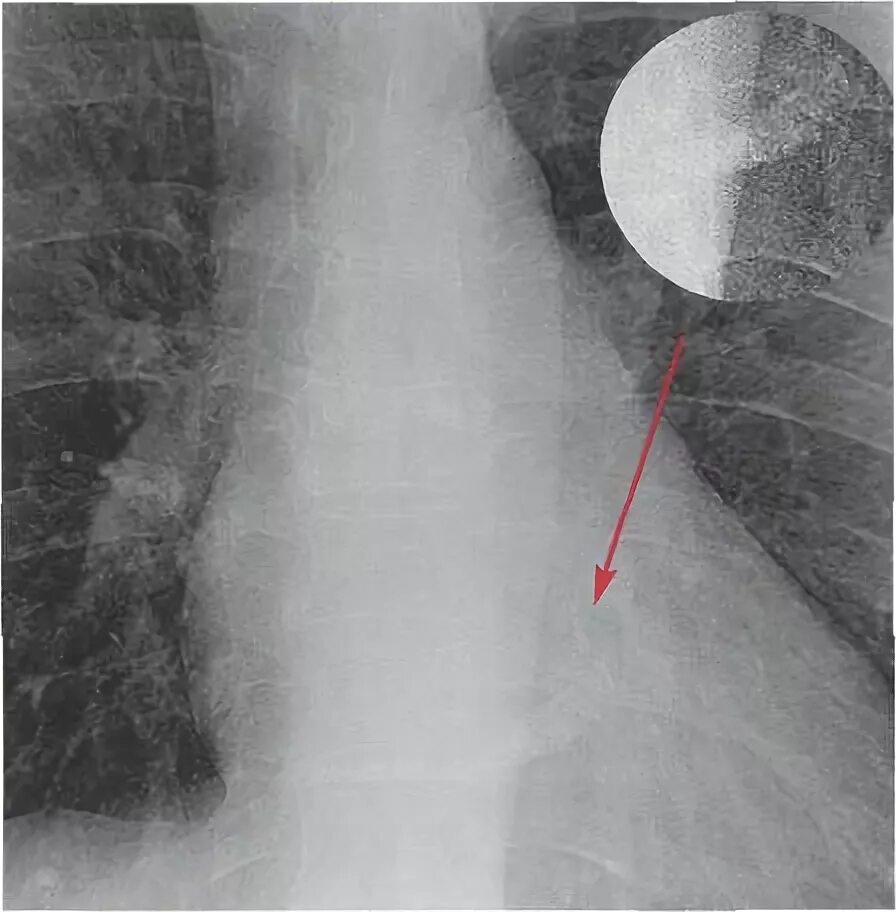

Обызвествление в проекции